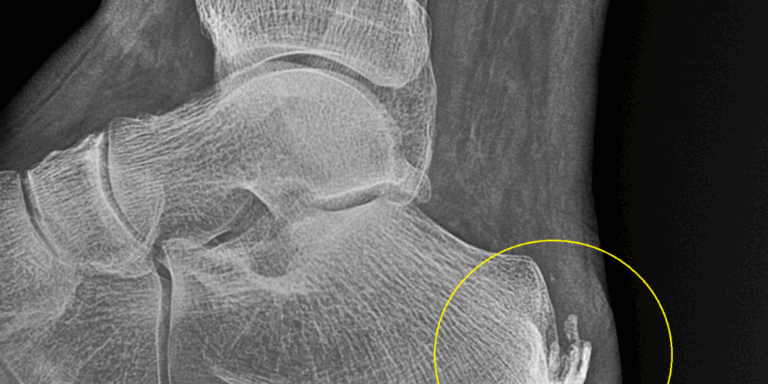

Calcificaciones en el tendón de Aquiles: causas y tratamiento

¿Qué son las calcificaciones en el tendón de Aquiles y cómo pueden afectarte? El tendón de Aquiles, también llamado tendón calcáneo, es una banda fibrosa…